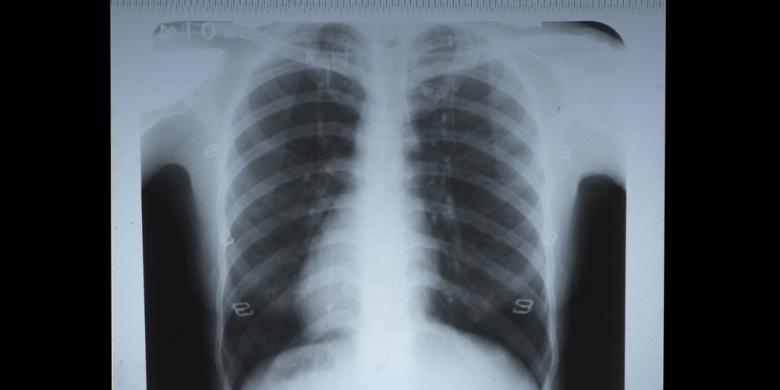

Setelah diperiksa, dokter yang bersangkutan menganjurkan dirontgen untuk melihat gigi bungsu saya yang baru tumbuh dan letaknya agak miring.